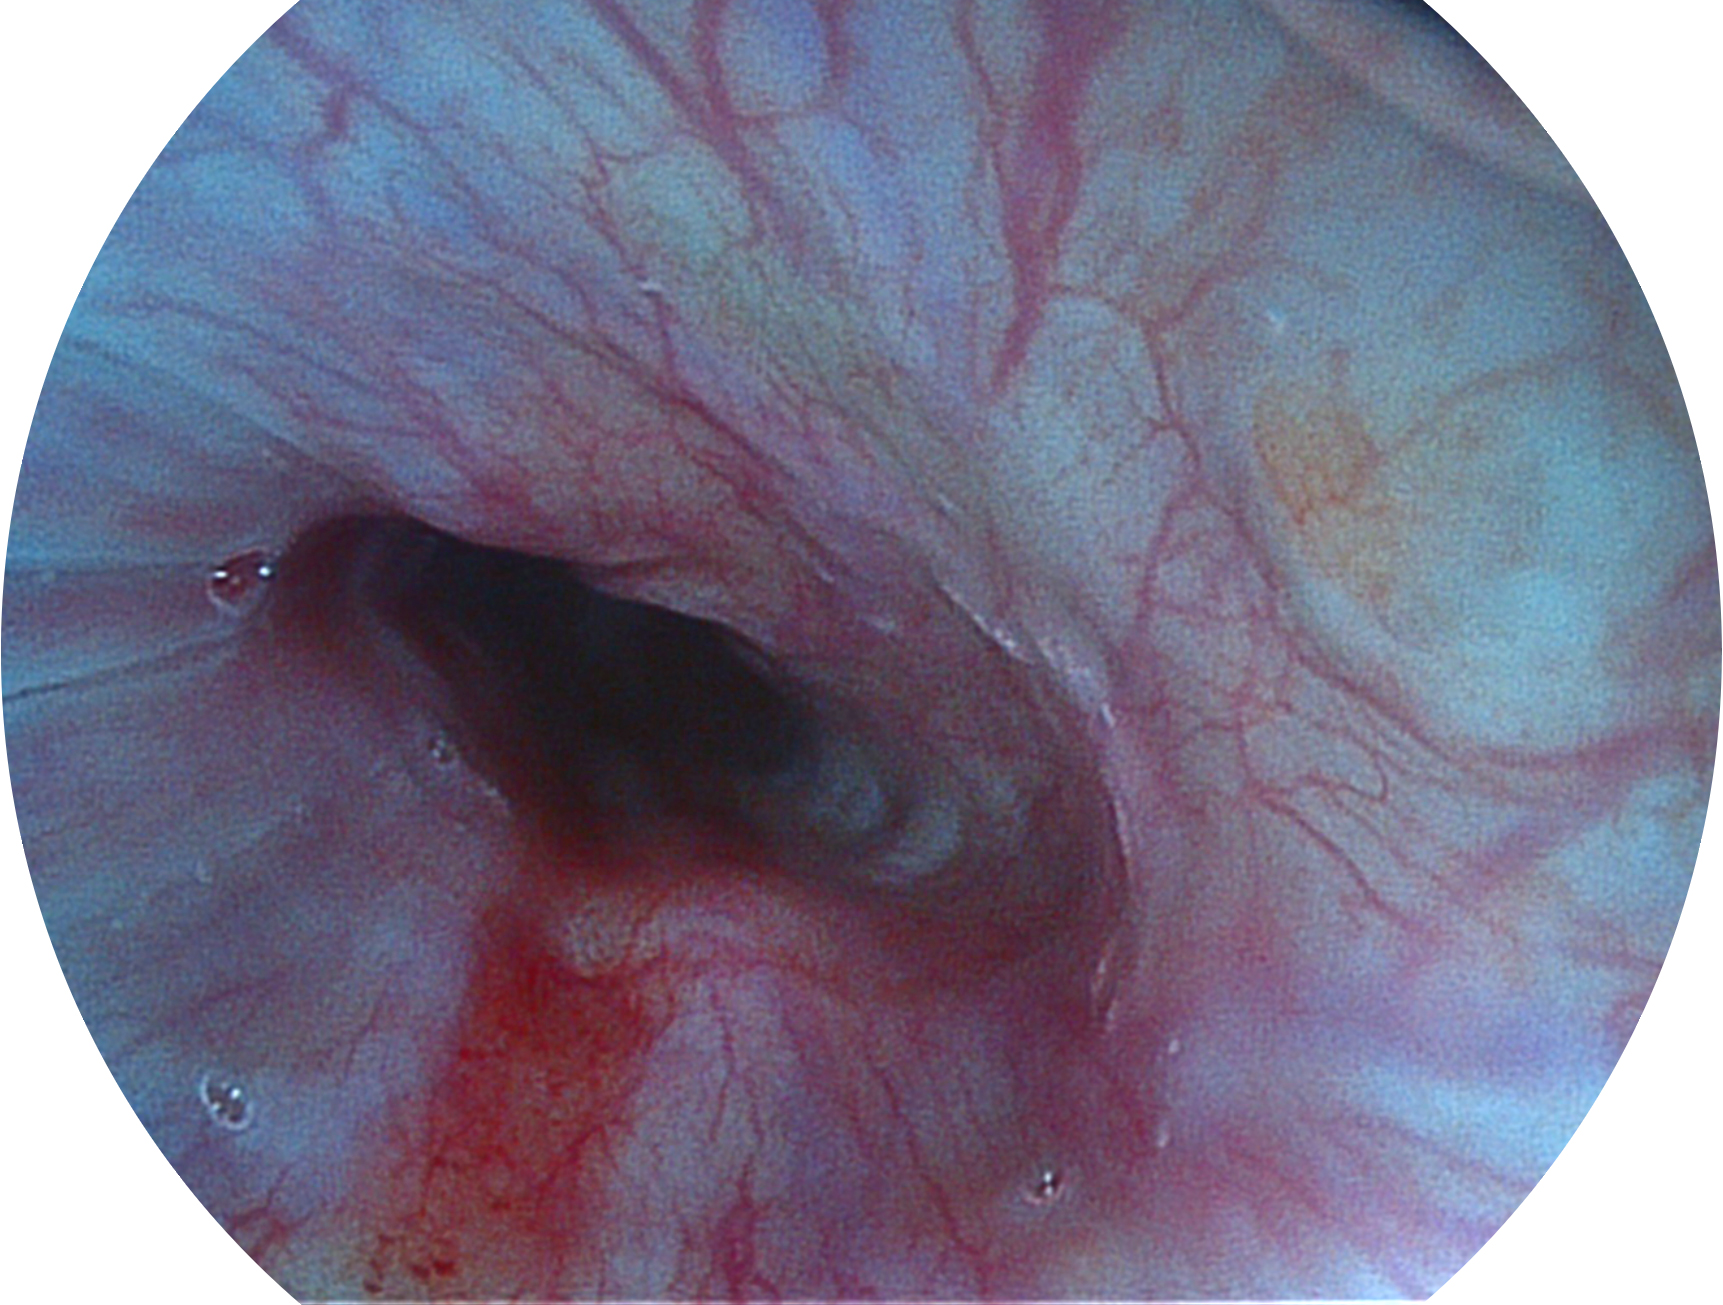

開立新開發(fā)的內(nèi)鏡染色技術(shù),主要是基于多波長LED 光源的開發(fā),VLS-55Q 四波長LED 光源是由四個(gè)不同顏色的LED光按照相應(yīng)照明模式所規(guī)定的特定發(fā)光比例進(jìn)行合束后形成,合束后形成的照明光的光譜由紅光、綠光、藍(lán)光及藍(lán)紫光這四個(gè)不同的波段范圍構(gòu)成。具有更高光譜自由度,通過光譜比例的控制,實(shí)現(xiàn)了聚譜成像技術(shù),英文全稱為“Spectral Focused Imaging, SFI”,縮寫為“SFI”和光電復(fù)合染色成像技術(shù),英文全稱為“Versatile Intelligent Staining Technology, VIST”,縮寫為“VIST”。